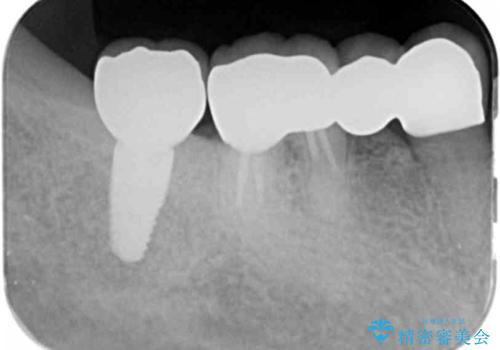

- 「歯がぐらぐらして噛めない、歯を抜いて欲しい、またしっかりと噛めるようになりたい。」、と歯周病治療を希望され来院されました。

歯の根本まで骨吸収が進み、ぐらぐらになってしまった歯を抜去し骨の造成を行ったのちインプラント治療を計画します。

重度に吸収してしまった歯槽骨をしっかりと造成を行ったのちにインプラント治療を行ったので、安定した歯周環境にすることができました。